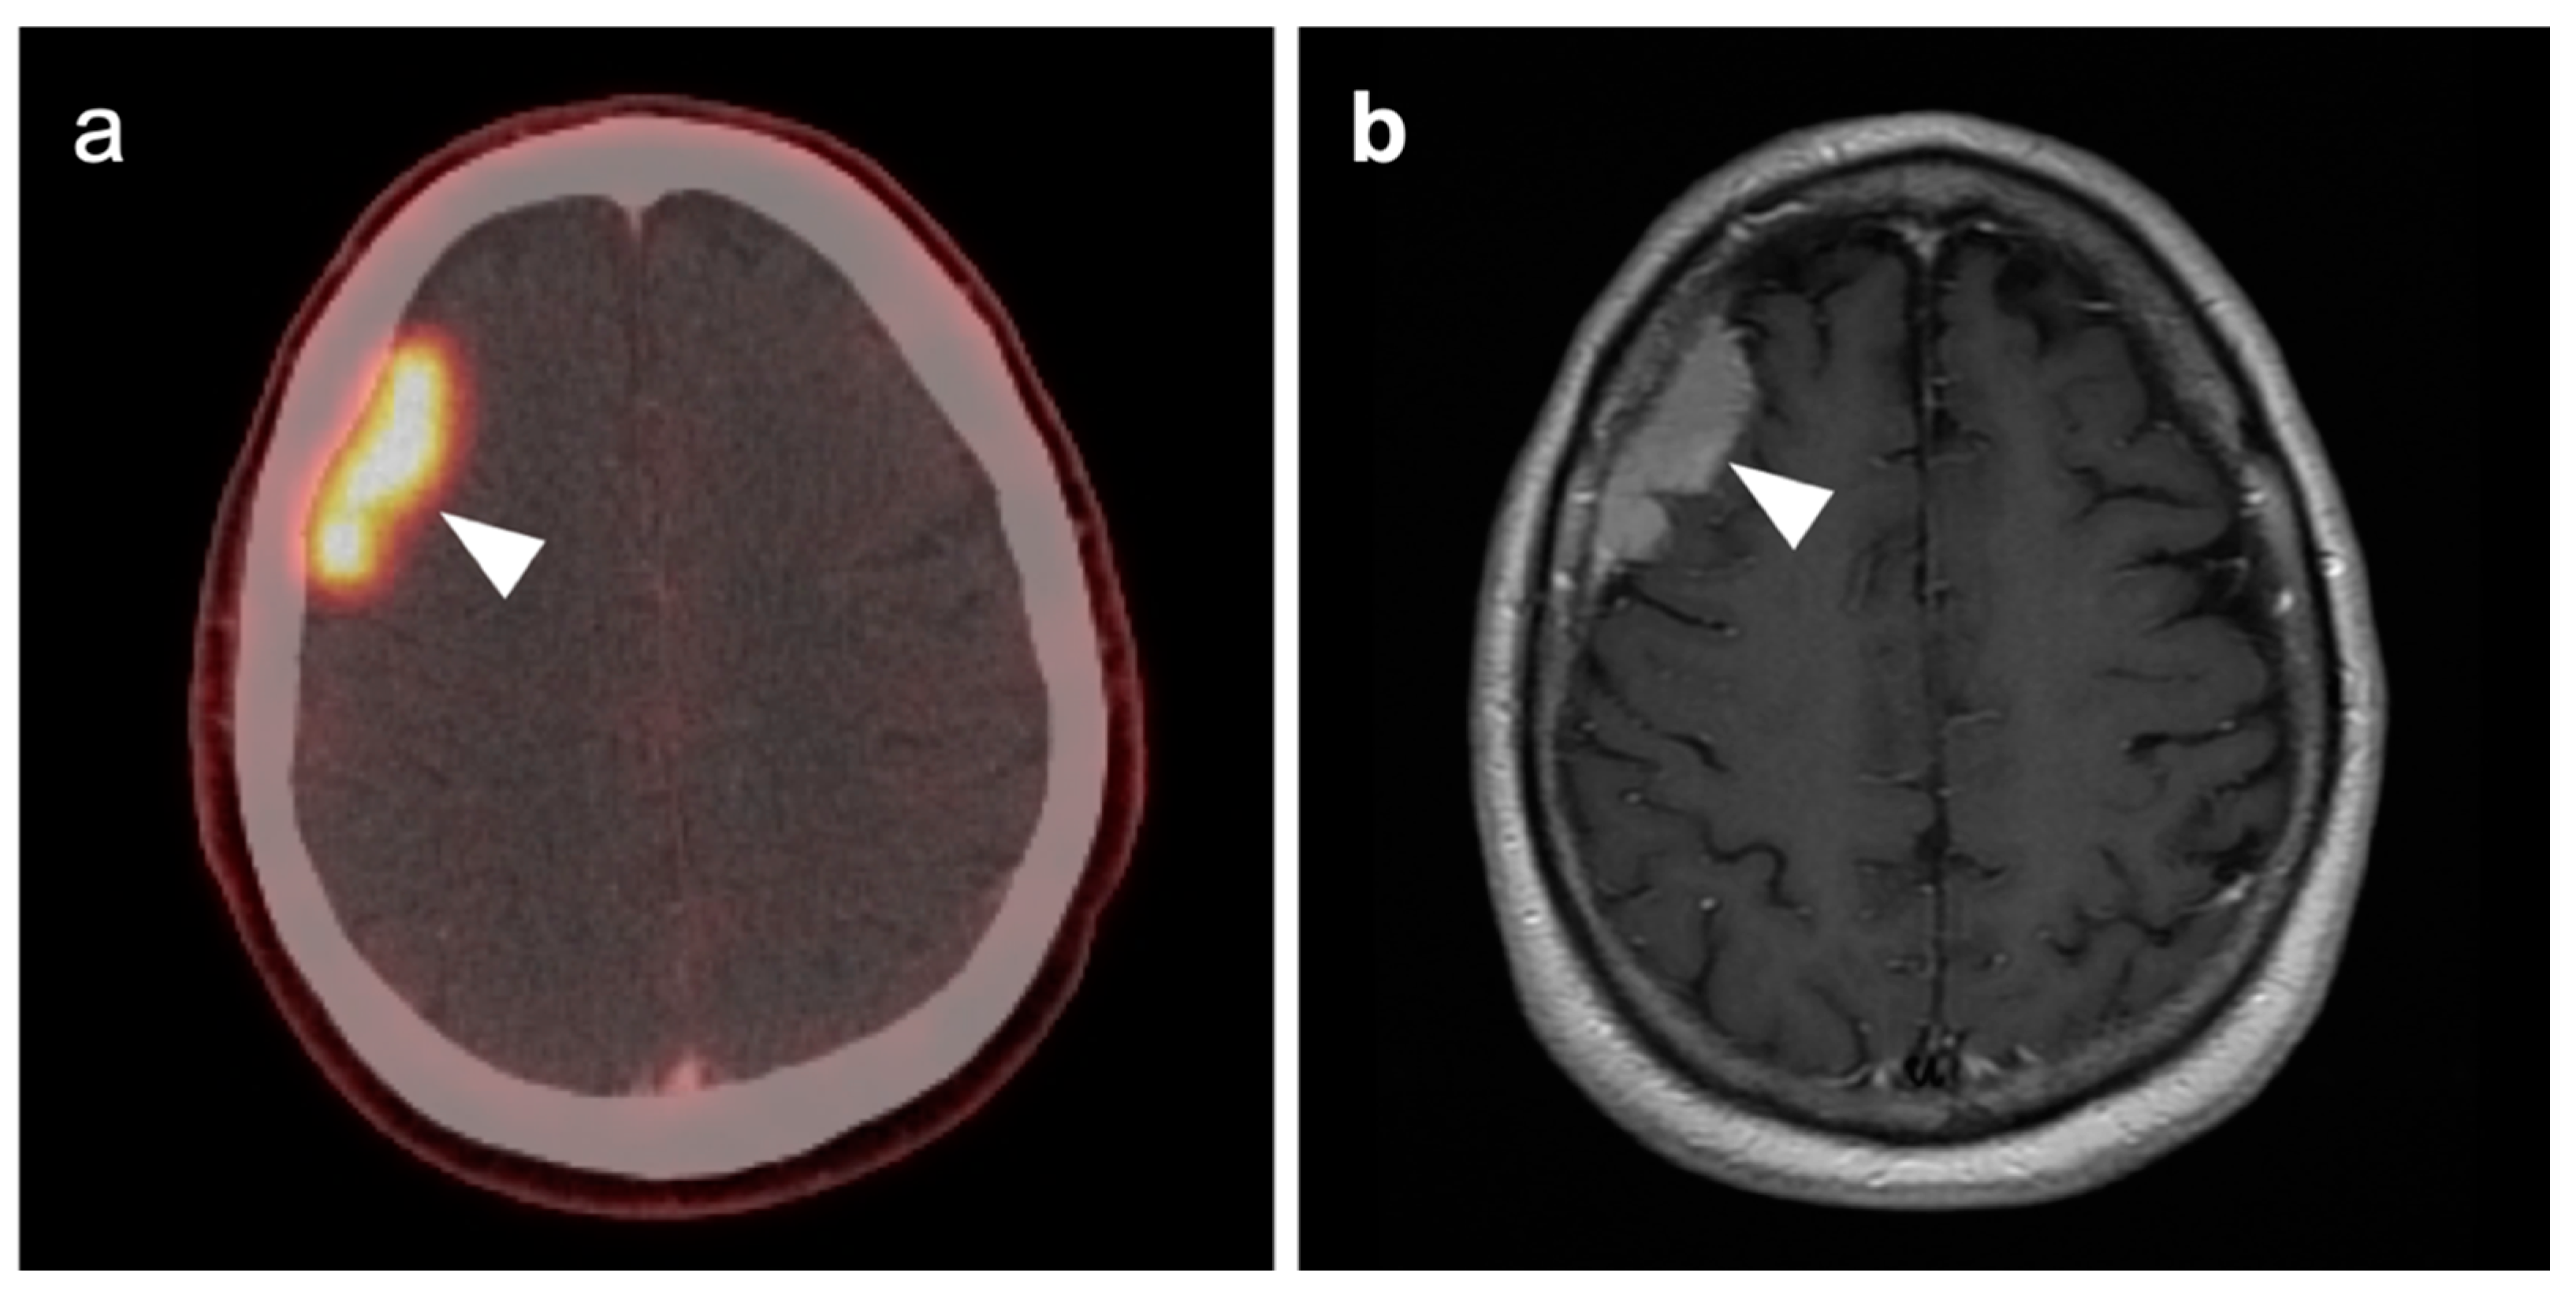

3.5. Brain Metastases

3.7. Meningioma